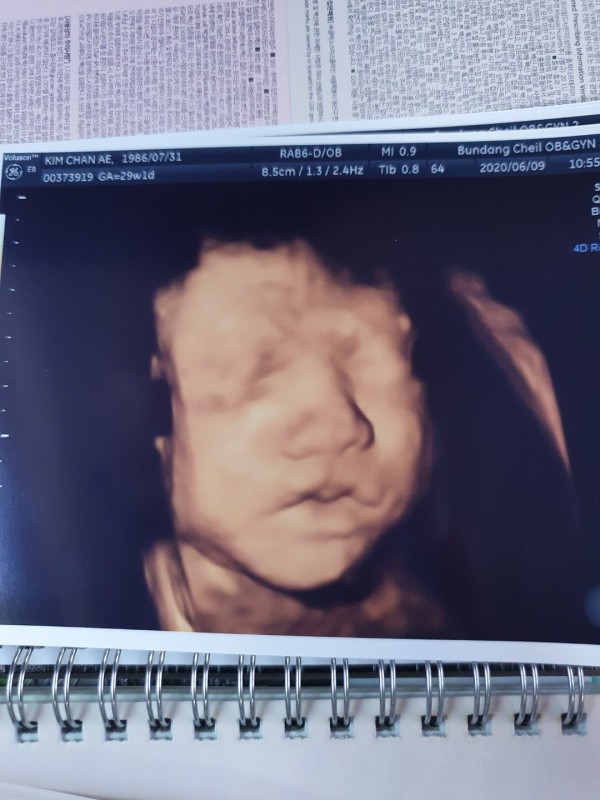

또한 주수에 맞춰 진찰에 가면 꼼꼼하게 초음파도 봐주시고 다양한 조언으로 무사히 37주에 접어들 수 있었습니다. 5월초에 입원 시에 다른 출산 후 입원한 산모들을 보며 부러워도 하고 언제 저희도 저 시기가 오나 많은 걱정도 하고 막막했지만 위혜정 선생님의 도움으로 인해 위험한 시기도 넘기고 오히려 지금은 아기가 너무 크지 않을까 걱정할 정도로 안정적인 상태가 되었습니다.

2020-08-13안녕하세요. 재현님! 이렇게 사랑이의 모습이 담긴 초음파와 예쁜 메모가 적힌 사진을 감사의 편지와 함께 보내주시어 너무 감사합니다. 사랑이에게 보내는 편지 속에서 사랑과 행복이 가득 전해지는 듯 합니다. 10달 가까이 되는 시간 동안 당황하고, 걱정되셨을 순간 또한 무사히 보내시어 이렇게 따뜻한 감동이 담겨 있는 감사의 말씀을 듣게 되어 도리어 본원 의료진 및 직원들이 더 큰 행복을 느낍니다. 사랑이와 만나는 순간까지 더욱 더 안전하고, 건강하실 수 있도록 노력하겠습니다. 감사합니다.